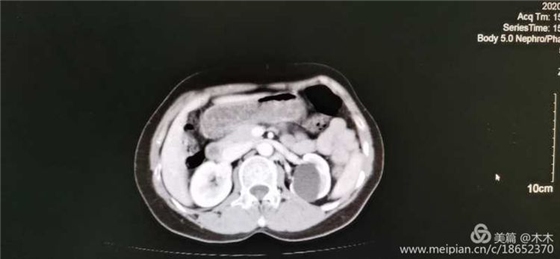

患者术前增强CT图片

近日,我院泌尿外科吴江河主任带领团队使用一次性电子输尿管软镜,完成首例经输尿管软镜下左肾盂旁囊肿内引流术,完全经自然通道手术,超微创,病人无切口痛苦创伤,恢复快,效果好,患者满意。